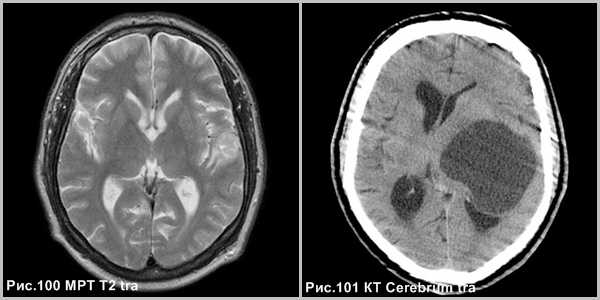

Плеоморфная ксантоастроцитома чаще кистозная (рис.101), реже солидная опухоль (рис.100) с излюбленной локализацией в височной доле, встречается в молодом возрасте.

КТ и МРТ проявления плеоморфной ксантоастроцитомы (ПКА): большая полушарная масса, тесно связанная с поверхностью мозга, с возможным участием ТМО. Поражение может быть неоднородным из-за образования кисты и кальцификации. В большинстве случаев, опухоль будет иметь вид кисты с пристеночным узлом, похожий на пилоцитарную астроцитому, с узелком, примыкающим к поверхности мозга. Хотя и в исключительных случаях, имеются чисто солидные ПКА [137]. Кистозное содержимое не отличается сигналом от ликвора [2].